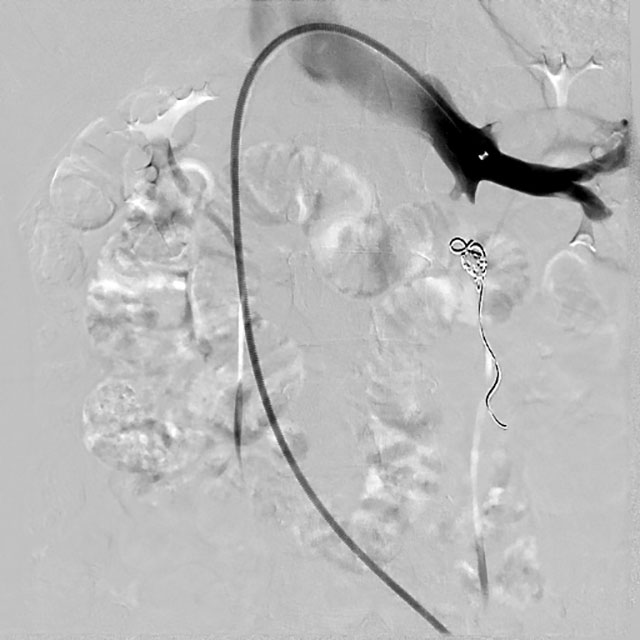

△栓塞前DSA造影提示:卵巢静脉返流、迂曲

入院后,超声检查进一步明确 “盆腔内探及曲张静脉”。介入・血管科徐燕能博士团队结合检查结果,为其制定了周密的介入手术方案 ——卵巢静脉造影 + 栓塞术。术中栓塞前的 DSA 造影显示,王女士存在 “卵巢静脉返流、迂曲” 的典型病变;而经过硬化、栓塞治疗后再次造影,卵巢静脉返流现象完全消失。